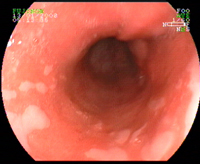

Dilatation endoscopique d'une sténose de l'oesophage